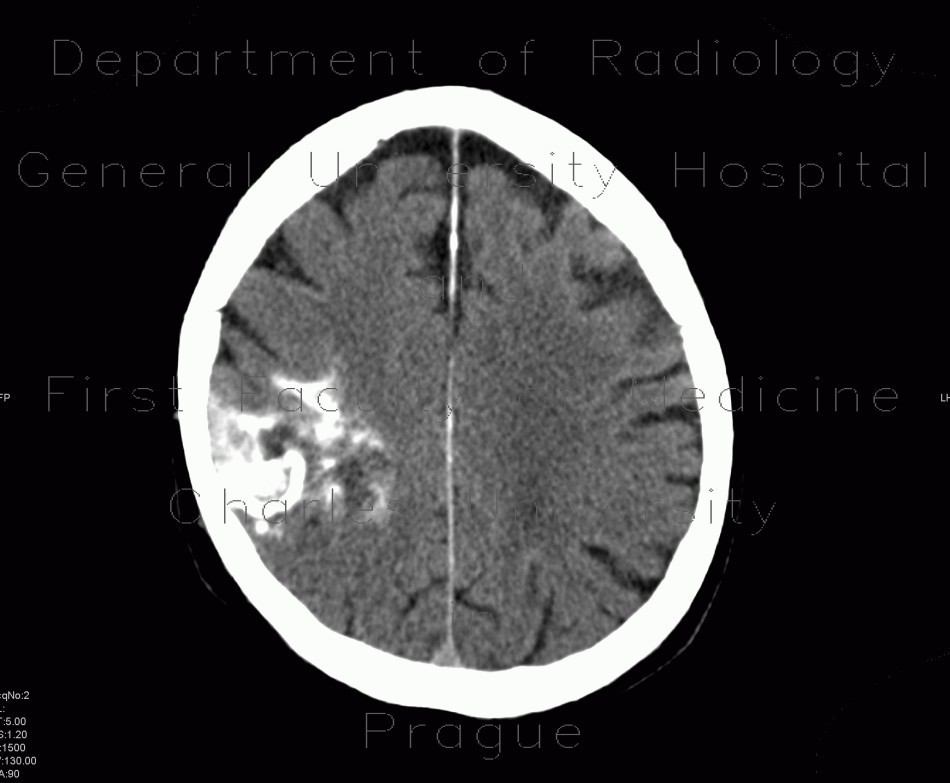

Which intra-cranial lesions are associated with marked surrounding oedema?

Metastasis Abscess Glioblastoma multiforme Radiation necrosis Hematoma (mild)

What is the DDx for a haemorrhagic tumour?

Glioblastoma multiforme: most common overall Metastasis: second most common overall Renal cell carcinoma Thyroid carcinoma Choriocarcinoma Melanoma Oligodendroglioma: second most common primary tumor